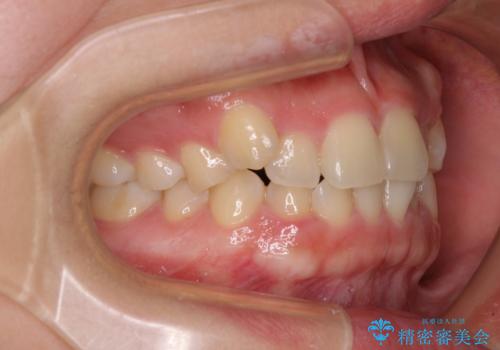

八重歯を治す 非抜歯のワイヤー矯正治療

- 左右の八重歯を気にして来院された患者様です。

八重歯である犬歯は歯根が長いため、上顎前歯が出っ歯になるリスクがあるため、必要に応じてアンカースクリューを用いて奥歯を後方に移動させる可能性をお伝えしました。

アンカースクリューを用いて、出っ歯仕上がりを回避し、正中位置も改善することができました。